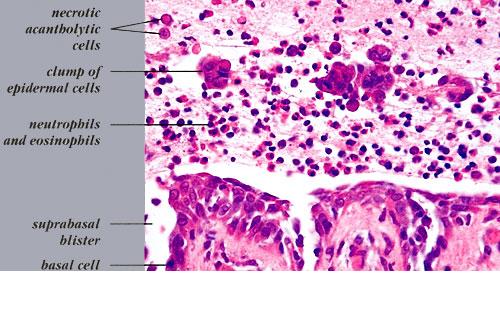

The earliest recognized change may be either eosinophilic spongiosis rarely or, more commonly, “spongiosis” in the lower epidermis . This spongiosis may actually represent the earliest manifestation of acantholysis rather than true spongiosis as defined earlier. Acantholysis leads first to the formation of clefts and then to blisters in a predominantly suprabasallocation . The intraepithelial acantholysis may extend into adnexal structures or occasionally be higher in the stratum spinosum. The basal keratinocytes, although separated from one another through the loss of attachment, remain firmly attached to the dermis like a “row of tombstones.” Within the blister cavity, the acantholytic keratinocytes, singularly or in clusters, have rounded condensed cytoplasm about an enlarged nucleus with peripherally palisaded chromatin and enlarged nucleoli. In some patients, there are varying quantities of antidesmoglein 1 and antidesmoglein 3 antibodies, leading to variable planes of acantholysis. There is little inflammation in the early phase of blister formation. If present, it is usually a sparse, lymphocytic perivascular infiltrate accompanied by dermal edema. However, if eosinophilic spongiosis is apparent, numerous eosinophils may infiltrate the dermis. The phenomenon of eosinophilic spongiosis occurs occasionally in other blistering diseases, particularly in their early phases, including acute contact dermatitis, pemphigus foliaceus, bullous pemphigoid, herpes gestation is, drug eruptions, spongiotic arthropod bite reactions, and transient acantholytic dermatosis. Several important changes ensue as the lesions age. First, a mixed inflammatory cell reaction consisting of neutrophils, lymphocytes, macrophages, and eosinophils may develop. Because of the instability of the blister roof, erosion and ulceration may occur. Older blisters may also have several layers of keratinocytes at the blister base because of keratinocyte migration and proliferation. Last, there may be considerable downward growth of epidermal strands, giving rise to so-called villi (Fig. 9-9D). The evaluation of patients with only oral lesions is difficult, because intact blisters are rarely encountered due to the trauma of mastication, and biopsies may show only erosion and ulceration. Indeed, it is best to sample the edge of a denuded area with intact mucosa in an attempt to demonstrate the typical pathologic changes. Clinicians frequently cannot distinguish between an ulcer and the intact mucosa, as both are often white and shaggy. In patients with only oral lesions, biopsies of intact oral mucosa for DIF testing are more sensitive than biopsies of lesions for routine light microscopic evaluation. Therefore, biopsy from the normal maxillary and upper buccal mucosa is necessary when there is extensive ulceration. Cytologic examination using a Tzanck preparation is useful for the rapid demonstration of acantholytic epidermal keratinocytes in the blisters of pemphigus vulgaris. For this